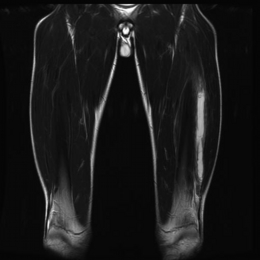

MRI:中間広筋断裂画像